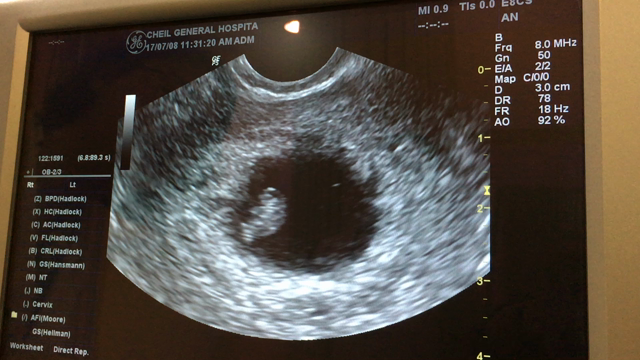

出張後の検診~9w5d~

出産予定日確定